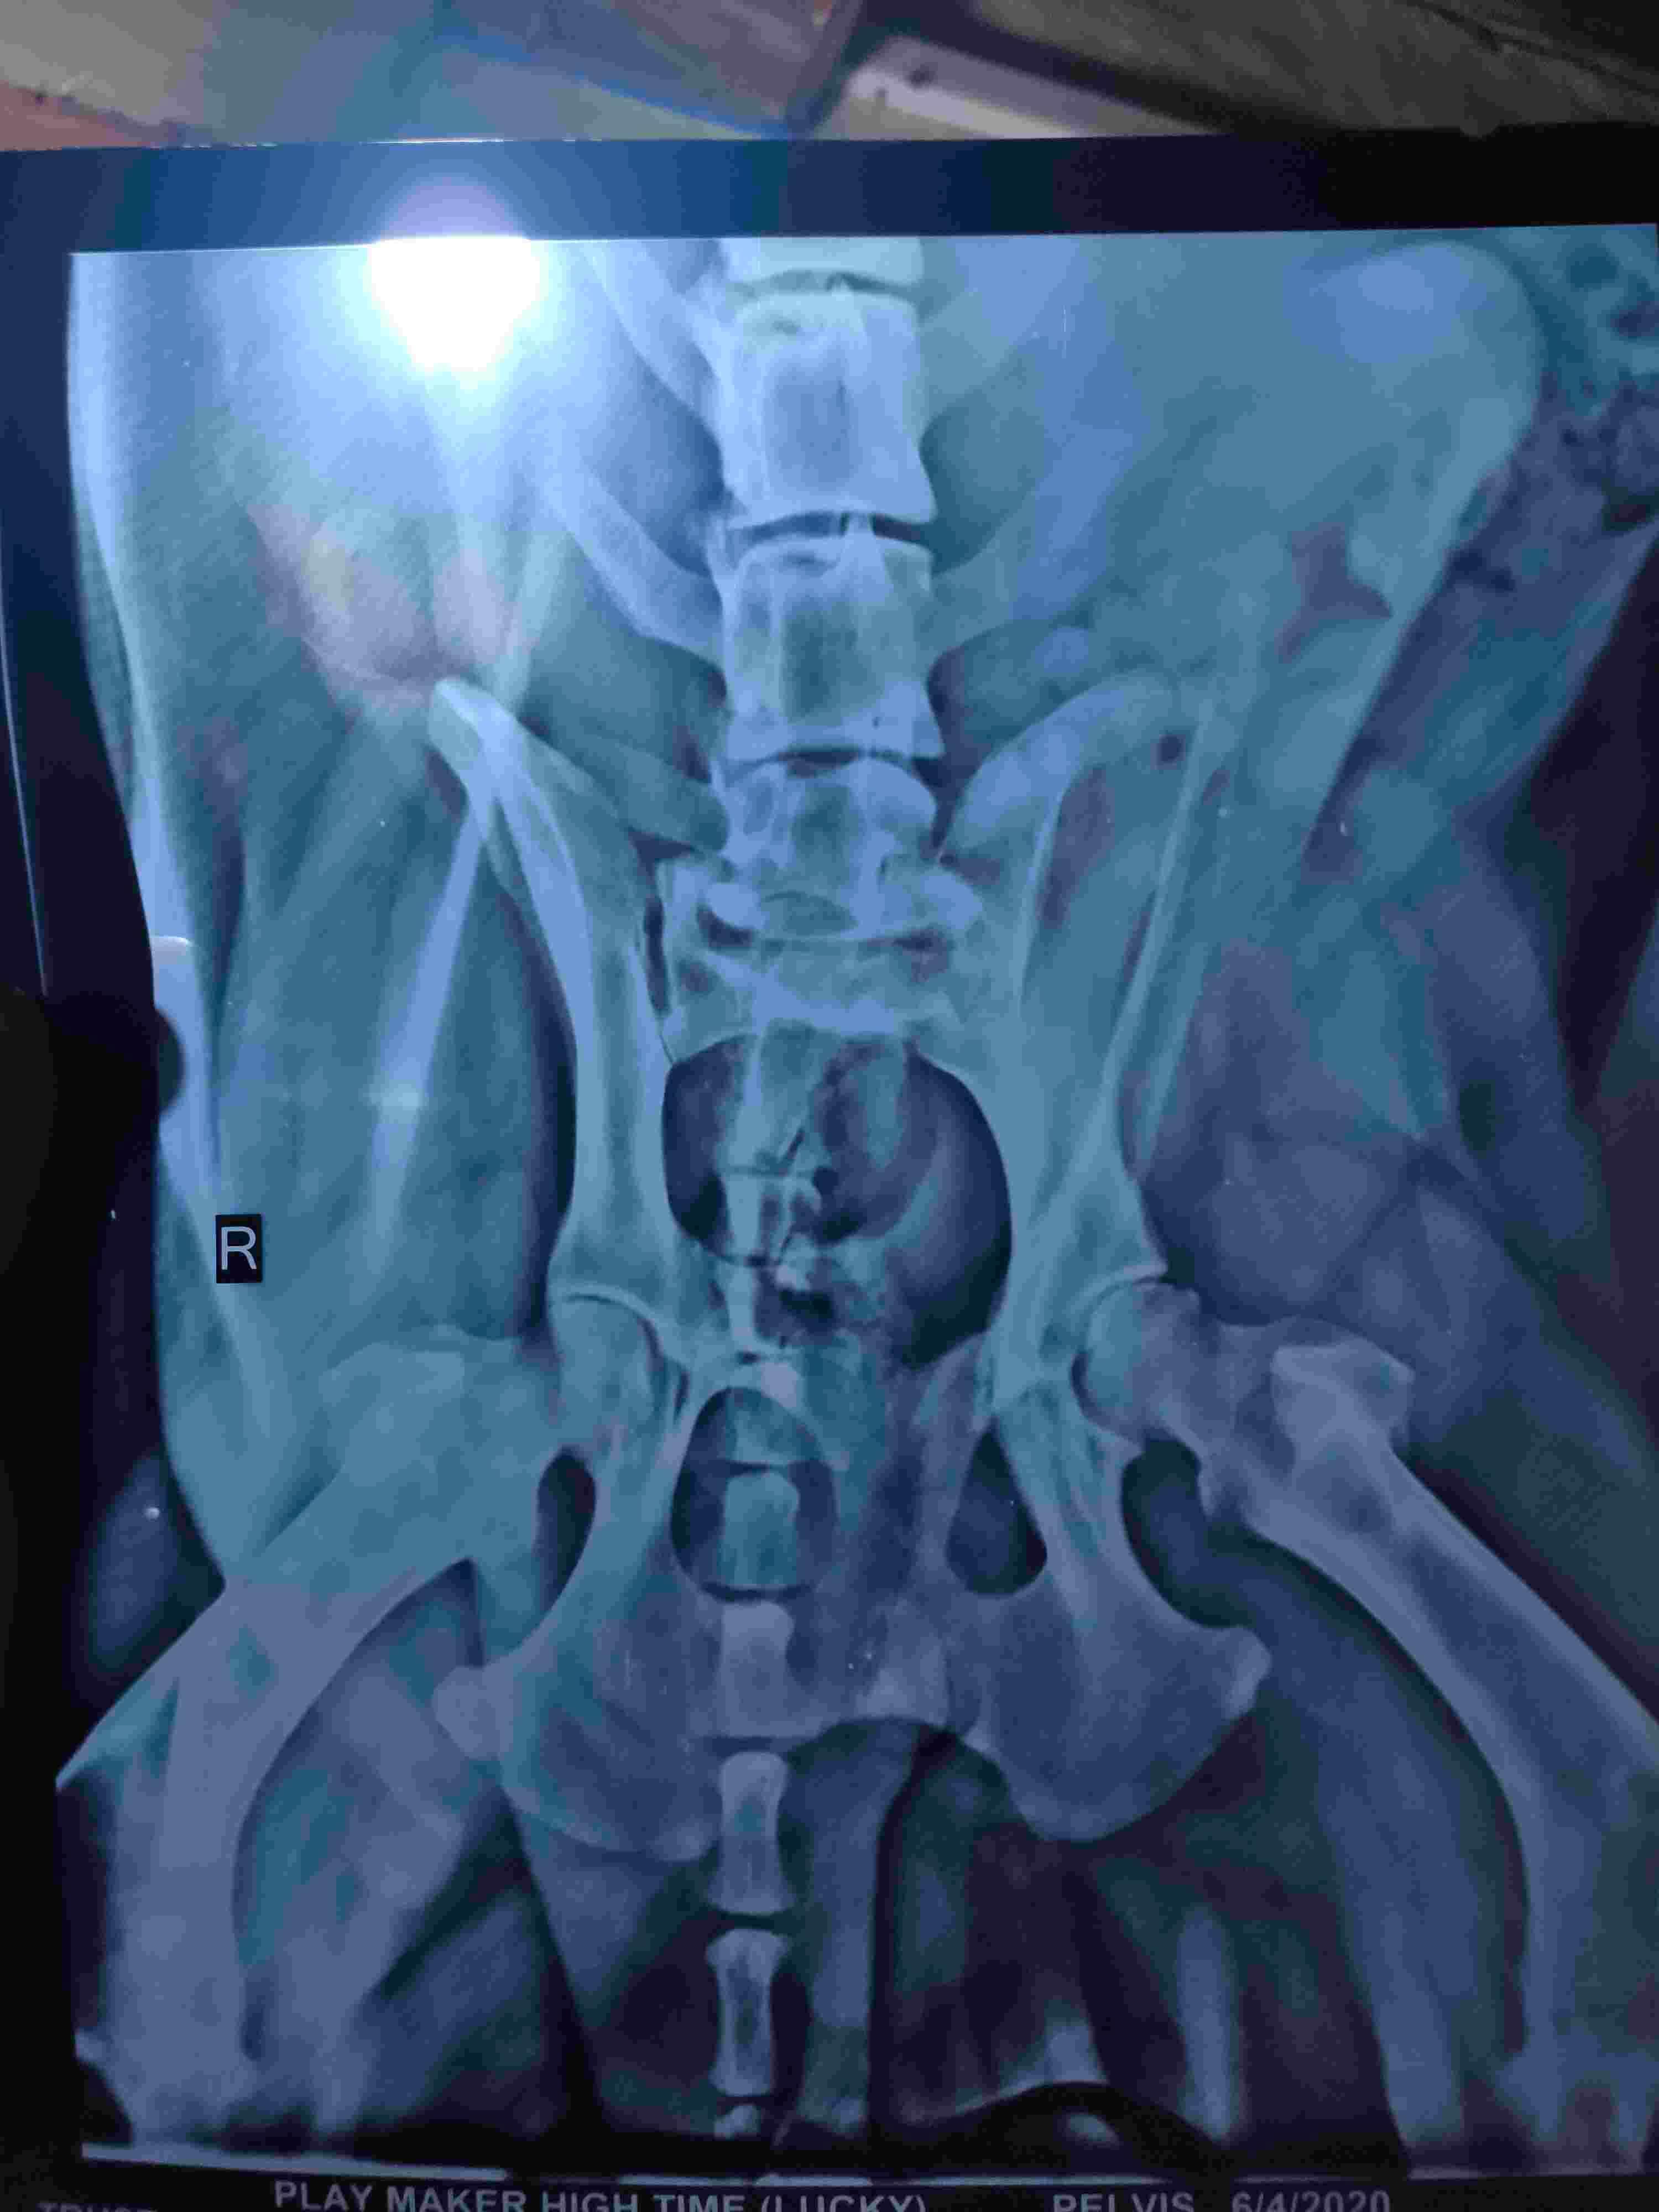

I am having a little trouble determine what is going on in the elbows. It looks like they are both fractured if these are pictures of different legs. The pelvis is also fractured. Treatment options would depend on the current condition of the pet and the cause for the injuries. Pelvic fractures often heal with strict cage rest for 1-2 months. The fracture of the elbow appears to have affected the joint, and it likely needs surgery to fix or amputation of the leg. If it is in both legs, surgery to fix the fractures is the best option.